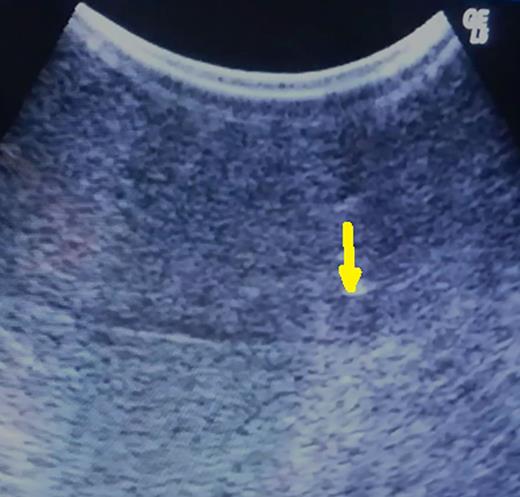

Based on preoperative image studies, the portion on the liver that contains the tumor is fully mobilized by transection of hepatic ligaments. Then, intraoperative ultrasonography is performed in order to achieve precise localization of the lesion and estimation of its deepness (Fig. 1).

Hypoechoic 5-mm lesion at 2 cm depth (metachronous metastatic tumor from colorectal carcinoma) (arrow).